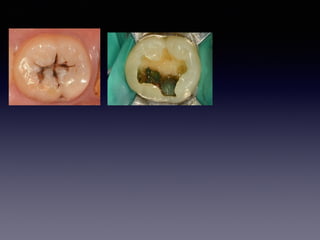

#6,#7,#8,#9,#29

partial pulputomy

follow-up case

(48 female)

2013 05 20

15m later

2013 05 21 #9

2013 05 27 #7

2013 06 04 #6,#8

2013 06 13 #29